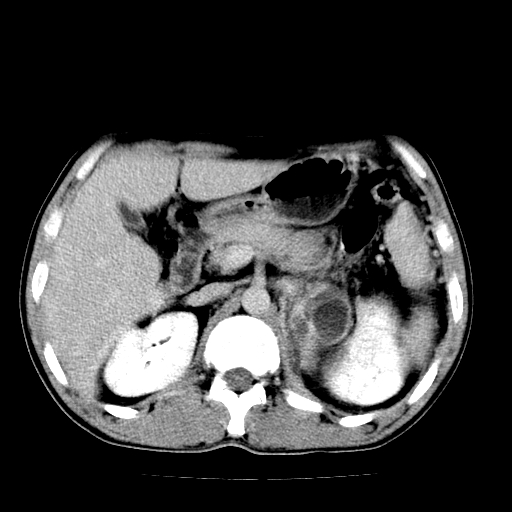

以下是引用天南地北在2007-4-30 13:36:00的发言:[br]支持慢性胰腺炎伴有假性囊肿

以下是引用andymaomao在2007-4-30 14:28:00的发言:[br]支持:1.慢性胰腺炎并假性囊肿形成可能;[br] 2.左肾形态稍增大,旋转不良。